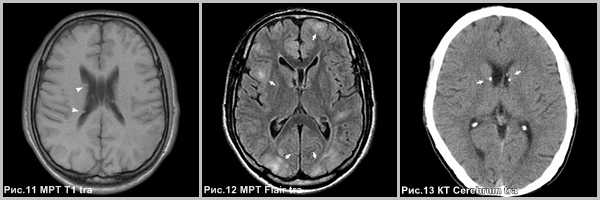

Что покажут снимки МРТ головного мозга при астроцитоме

- Очаг с объемным воздействием незначительно выраженный перифокальный отек

- Т1-ВИ: киста, гипоинтенсивная по отношению к белому веществу, и изоинтенсивный солидный компонент опухоли

- Т2-ВИ: гиперинтенсивный кистозный и изоинтенсивный солидный компоненты опухоли

- FLAIR-изображение: гипоинтенсивный кистозный и гиперинтенсивный солидный компоненты опухоли

- Т1-ВИ после введения КС: выраженное асимметричное контрастное усиление.

2. КТ при пилоцитарной астроцитоме:

• Бесконтрастная КТ:

о Обособленное объемное образование с кистозным и солидным компонентами

о Перифокальный отек слабо выражен или отсутствует

о Солидный компонент гипо- или изоденсен по отношению к серому веществу (СВ)

о Са++ в 20% случаев, редко геморрагический компонент

о Часто вызывает обструктивную гидроцефалии в зависимости от локализации

• КТ с контрастированием:

о > 95% опухолей накапливают контраст (характер вариабелен):

- Неконтрастируемый кистозный компонент, выраженное контрастирование пристеночного солидного компонента в 50% случаев

- Солидный компонент с некротизированным центральным отделом, гетерогенный характер контрастирования в 40% случаев

- Солидный гомогенный компонент в 10% случаев

- Кистозный компонент может накапливать контраст на отсроченных изображениях

- Может наблюдаться некоторое контрастирование стенки кистозного компонента